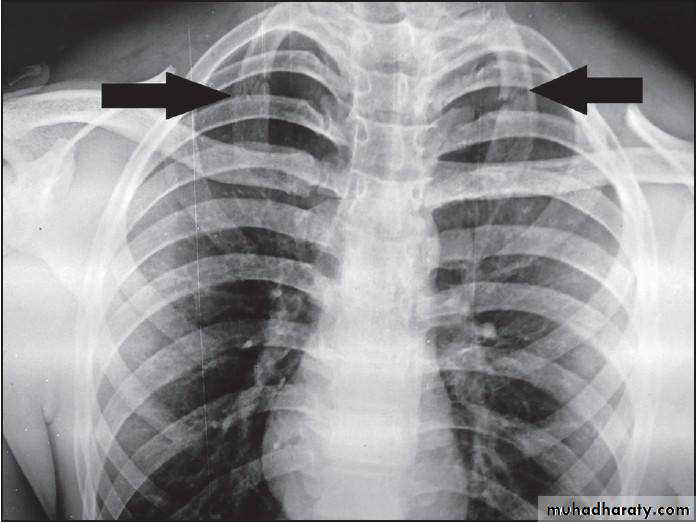

First rib fracture